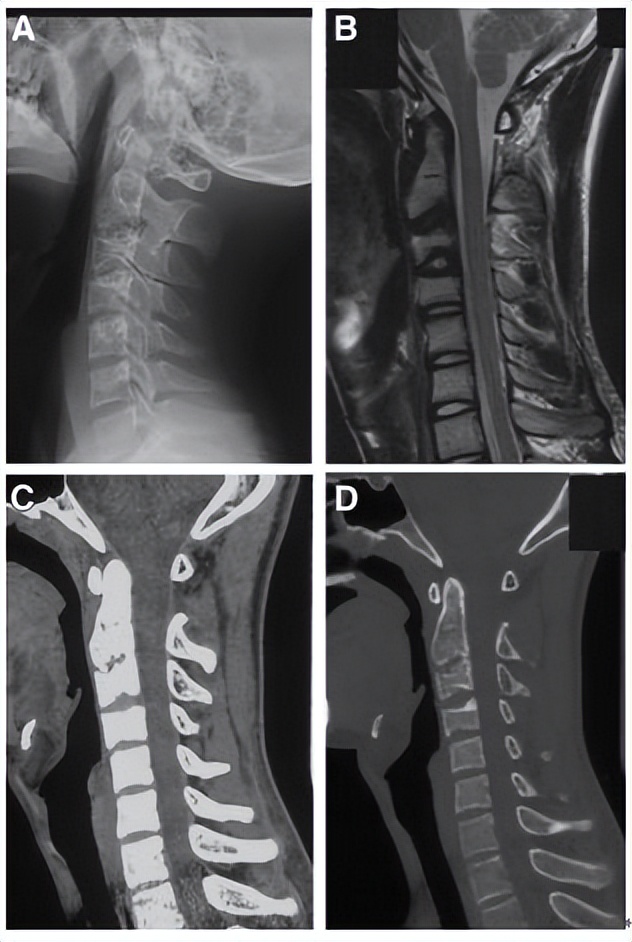

一位88岁女性患者,主诉急性颈痛伴发热2个月入院。体温波动在38-39.3℃,无视力模糊,无神经及脊髓压迫征象。颈椎CT+矢状位重建显示寰椎横韧带的曲线状钙化(图A,箭头所示),线性钙化(图B,箭头所示),以及齿状突周围的冠状钙沉积(图C,箭头所示)。给予短期非甾体抗炎药和泼尼松龙(15mg/d)后,其上述症状完全缓解。同时,作者指出这类疾病通常不需要长期用药。